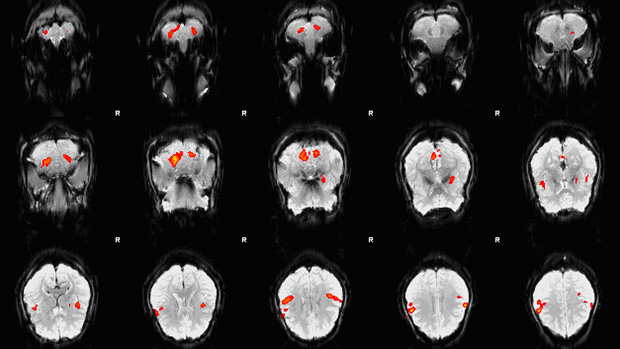

Picture of an fMRI scan showing brain activity in particular locations of the brain

Functional MRI scans can pin-point the location of brain activity. Image source: Zereshk / Wikicommons.